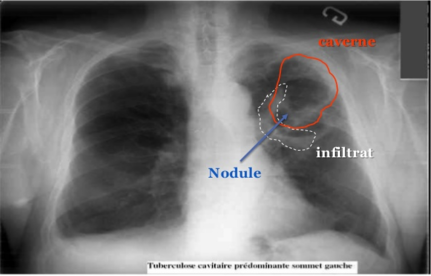

Casablanca: lancement des travaux de construction du premier Centre de diagnostic et d’expertise sur la tuberculose